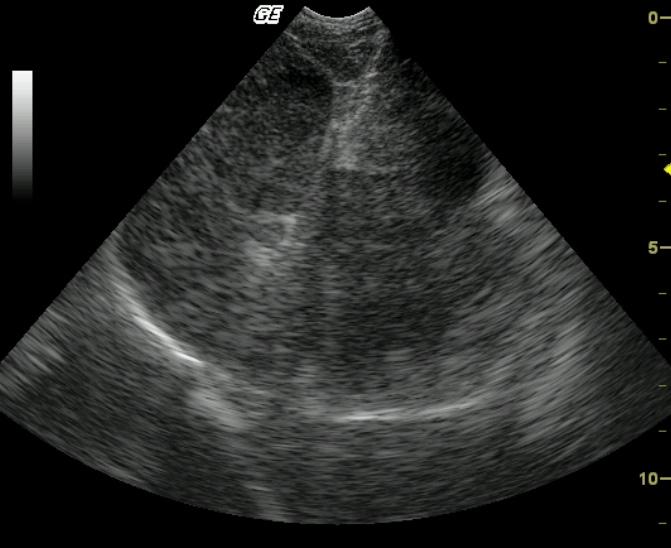

A 10 year old MN Pug was presented for the evaluation of anorexia, vomiting, diarrhea, and pollakuria. No abnormalities were noted on the physical exam. The CBC showed a neutrophilia, monocytosis, and thrombocytopenia. A serum biochemical profile revealed elevated serum alkaline phosphatase, elevated ALT, elevated AST, elevated GGT enzyme activities as well as hypercholesterolemia.